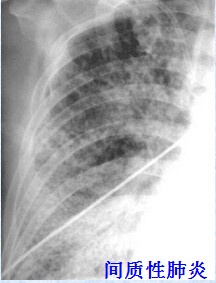

病毒性肺炎:

多见双肺下叶弥漫性密度均匀的小结节状浸润阴影,边缘模糊,少数患者可见叶性浸润或弥漫性网状结节性浸润灶。